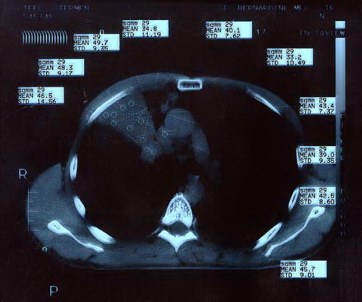

Scan 15th March 1999 No1